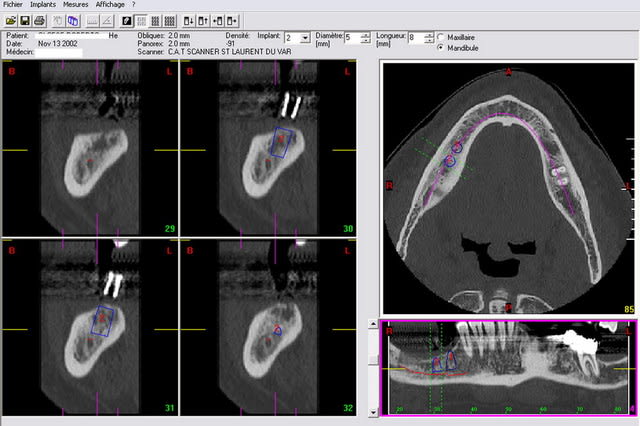

Troisieme image, la simulation avec un implant de 8mm X diam 5mm. je sais c'est court mais même un 10 mm ne passe pas...